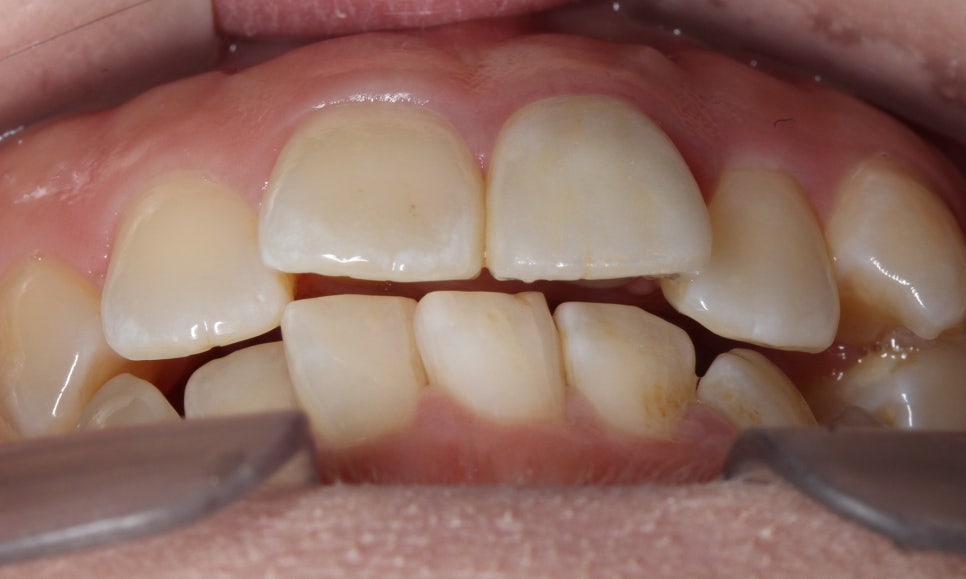

위의 구내사진을 보시면 사진에서

상악 우측 부분의 송곳니가

덧니처럼 맹출되어 있는 것을 확인할 수 있습니다.

정면에서 보면 치아가 순측으로

뻐드러져 있는 모습인데요,

전체적으로 전치부의 치열이

삐뚤거리고 한쪽 방향으로

치우쳐져 있는 모습입니다.